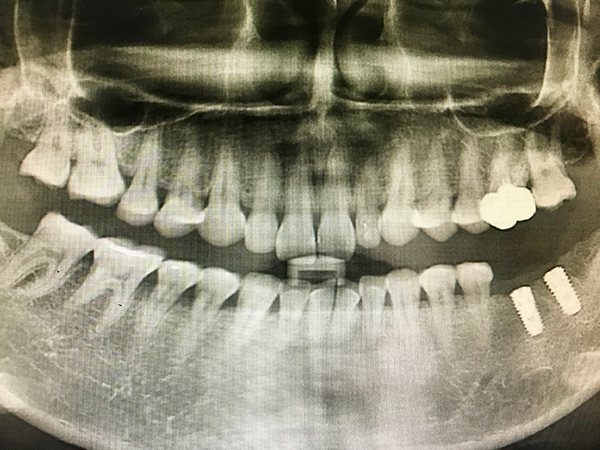

임플란트 치료 기간의 가장 중요한 포인트는 바로 잇몸뼈의 여부입니다. 만약 잇몸뼈가 충분하다면 일반적으로 3~4개월 정도면 충분할 수 있는데, 잇몸뼈가 부족하다면 뼈이식을 해야 하므로 기간이 더 길어질 수 있습니다. 잇몸뼈가 부족한 경우 뼈이식 수술을 통해 잇몸뼈를 보강해야 하며, 이는 임플란트 치료 기간을 6개월 이상으로 연장할 수 있습니다. 따라서 초기 상담 시 잇몸뼈 상태를 정확히 진단받는 것이 중요합니다.

또한, 임플란트의 위치에 따라 치료 기간이 달라지는데, 상악의 경우엔 5개월 ~ 6개월 정도가 소요되고, 하악의 경우 3개월 ~ 4개월 정도가 소요되는 것이 일반적입니다. 하악은 상악에 비해 치조골의 밀도가 높다 보니 하악 쪽이 치료 기간이 더 단축되는 것입니다. 상악의 경우 부비동이 가까워 추가적인 뼈이식이 필요한 경우가 많아 치료 기간이 더 길어질 수 있습니다.